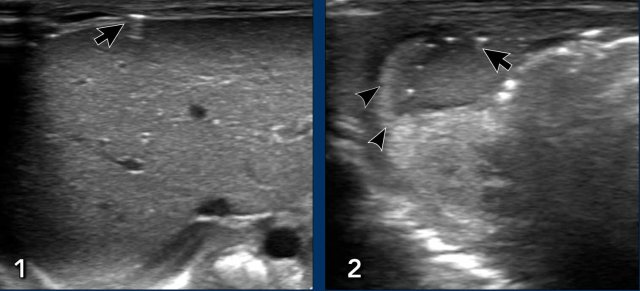

Images

- Diseased bowel wall: thickened and echogenic bowel, with interspersed ascites.

- Thinned and irregular bowel wall in progressive NEC.

Doppler image showing absence of flow and presence of pneumatosis intestinalis.

Courtesy of prof dr M Epelman, RadioGraphics 2007

- A little air bubble overlying the liver (arrow).

- ‘Dirty ascites’: echogenic ascites (arrowheads) with some air bubbles in the fluid collection (arrows).